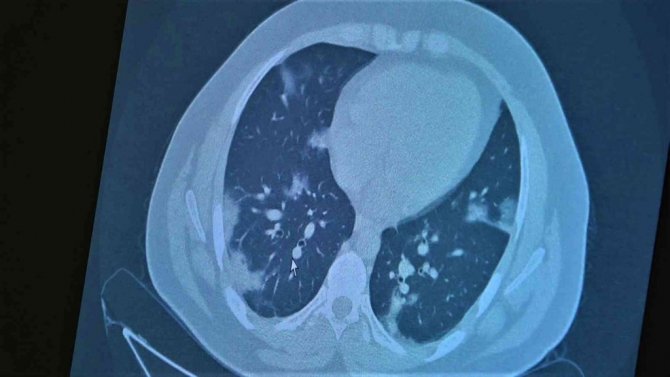

Korona virüsün mutasyona uğramış hali artık aşısız çocuklara ciddi zararlar vermeye başladığına dikkat çeken Göğüs Hastalıkları Uzm. Prof. Dr. Özkaya, 11 ve 14 yaşlarındaki koronaya yakalanmış ve ciddi akciğer tutulumlarıyla tedavi gören çocukların akciğer tomografilerini gözler önüne serdi.

Çocukların akciğer tomografilerini inceleyen Özkaya, "11 yaşında kovid pozitif bir öğrencimiz, yüksek ateş ve nefes darlığı ile bize geldi. Ciddi akciğer tutulumu var. Geçen yıl "bu çocuklar hastalıktan etkilenmiyor" diyorduk. Bu çocukta görüyorsunuz buzlu camlar ve konsolidasyon alanlarla seyrediyor. Geçen yıl bu şekilde çok çocuk görmüyorduk. Önümüzdeki aylarda bu şekilde devam ederse çocuklarımızı kaybetmeye bile başlayabiliriz. 14 yaşında pozitif olan bir diğer çocuğumuz ise aşı randevusu almış ama aşısını olmadan ateş ve öksürükle başvurdu. Halen şanslıyız. Çocuklar çok hızlı tedaviye yanıt veriyor. Düzeldi. Çekilen tomografisinde ise bilaterel yaygın tutulumları vardı. Bu ise 24 yaşında genç hastanın akciğer tomografisi. Bu kişide yaygın akciğer tutulumları görüldü. Bunu da tedavi ettik. Önümüzdeki aylarda ne getirecek ne götürecek beraber göreceğiz. Özellikle havaların soğumasıyla kapalı ortamlarda geçilen zamanın ve kalabalıkların etkisiyle vaka sayılarının önümüzdeki günlerde artacağını biliyoruz. Şu an gerçekten hastalık gençlerde 30 -40 yaş altı gençlerde görülmeye başladı. Poliklinik şartlarında olanların büyük bir kısmı 30 yaş altı hastalar. Servislerde yatanlarda orta yaş ve altı nüfus. Yoğun bakımda yatanların büyük bir kısmı ise aşısız erişkin insanlardan oluşuyor" diye konuştu.